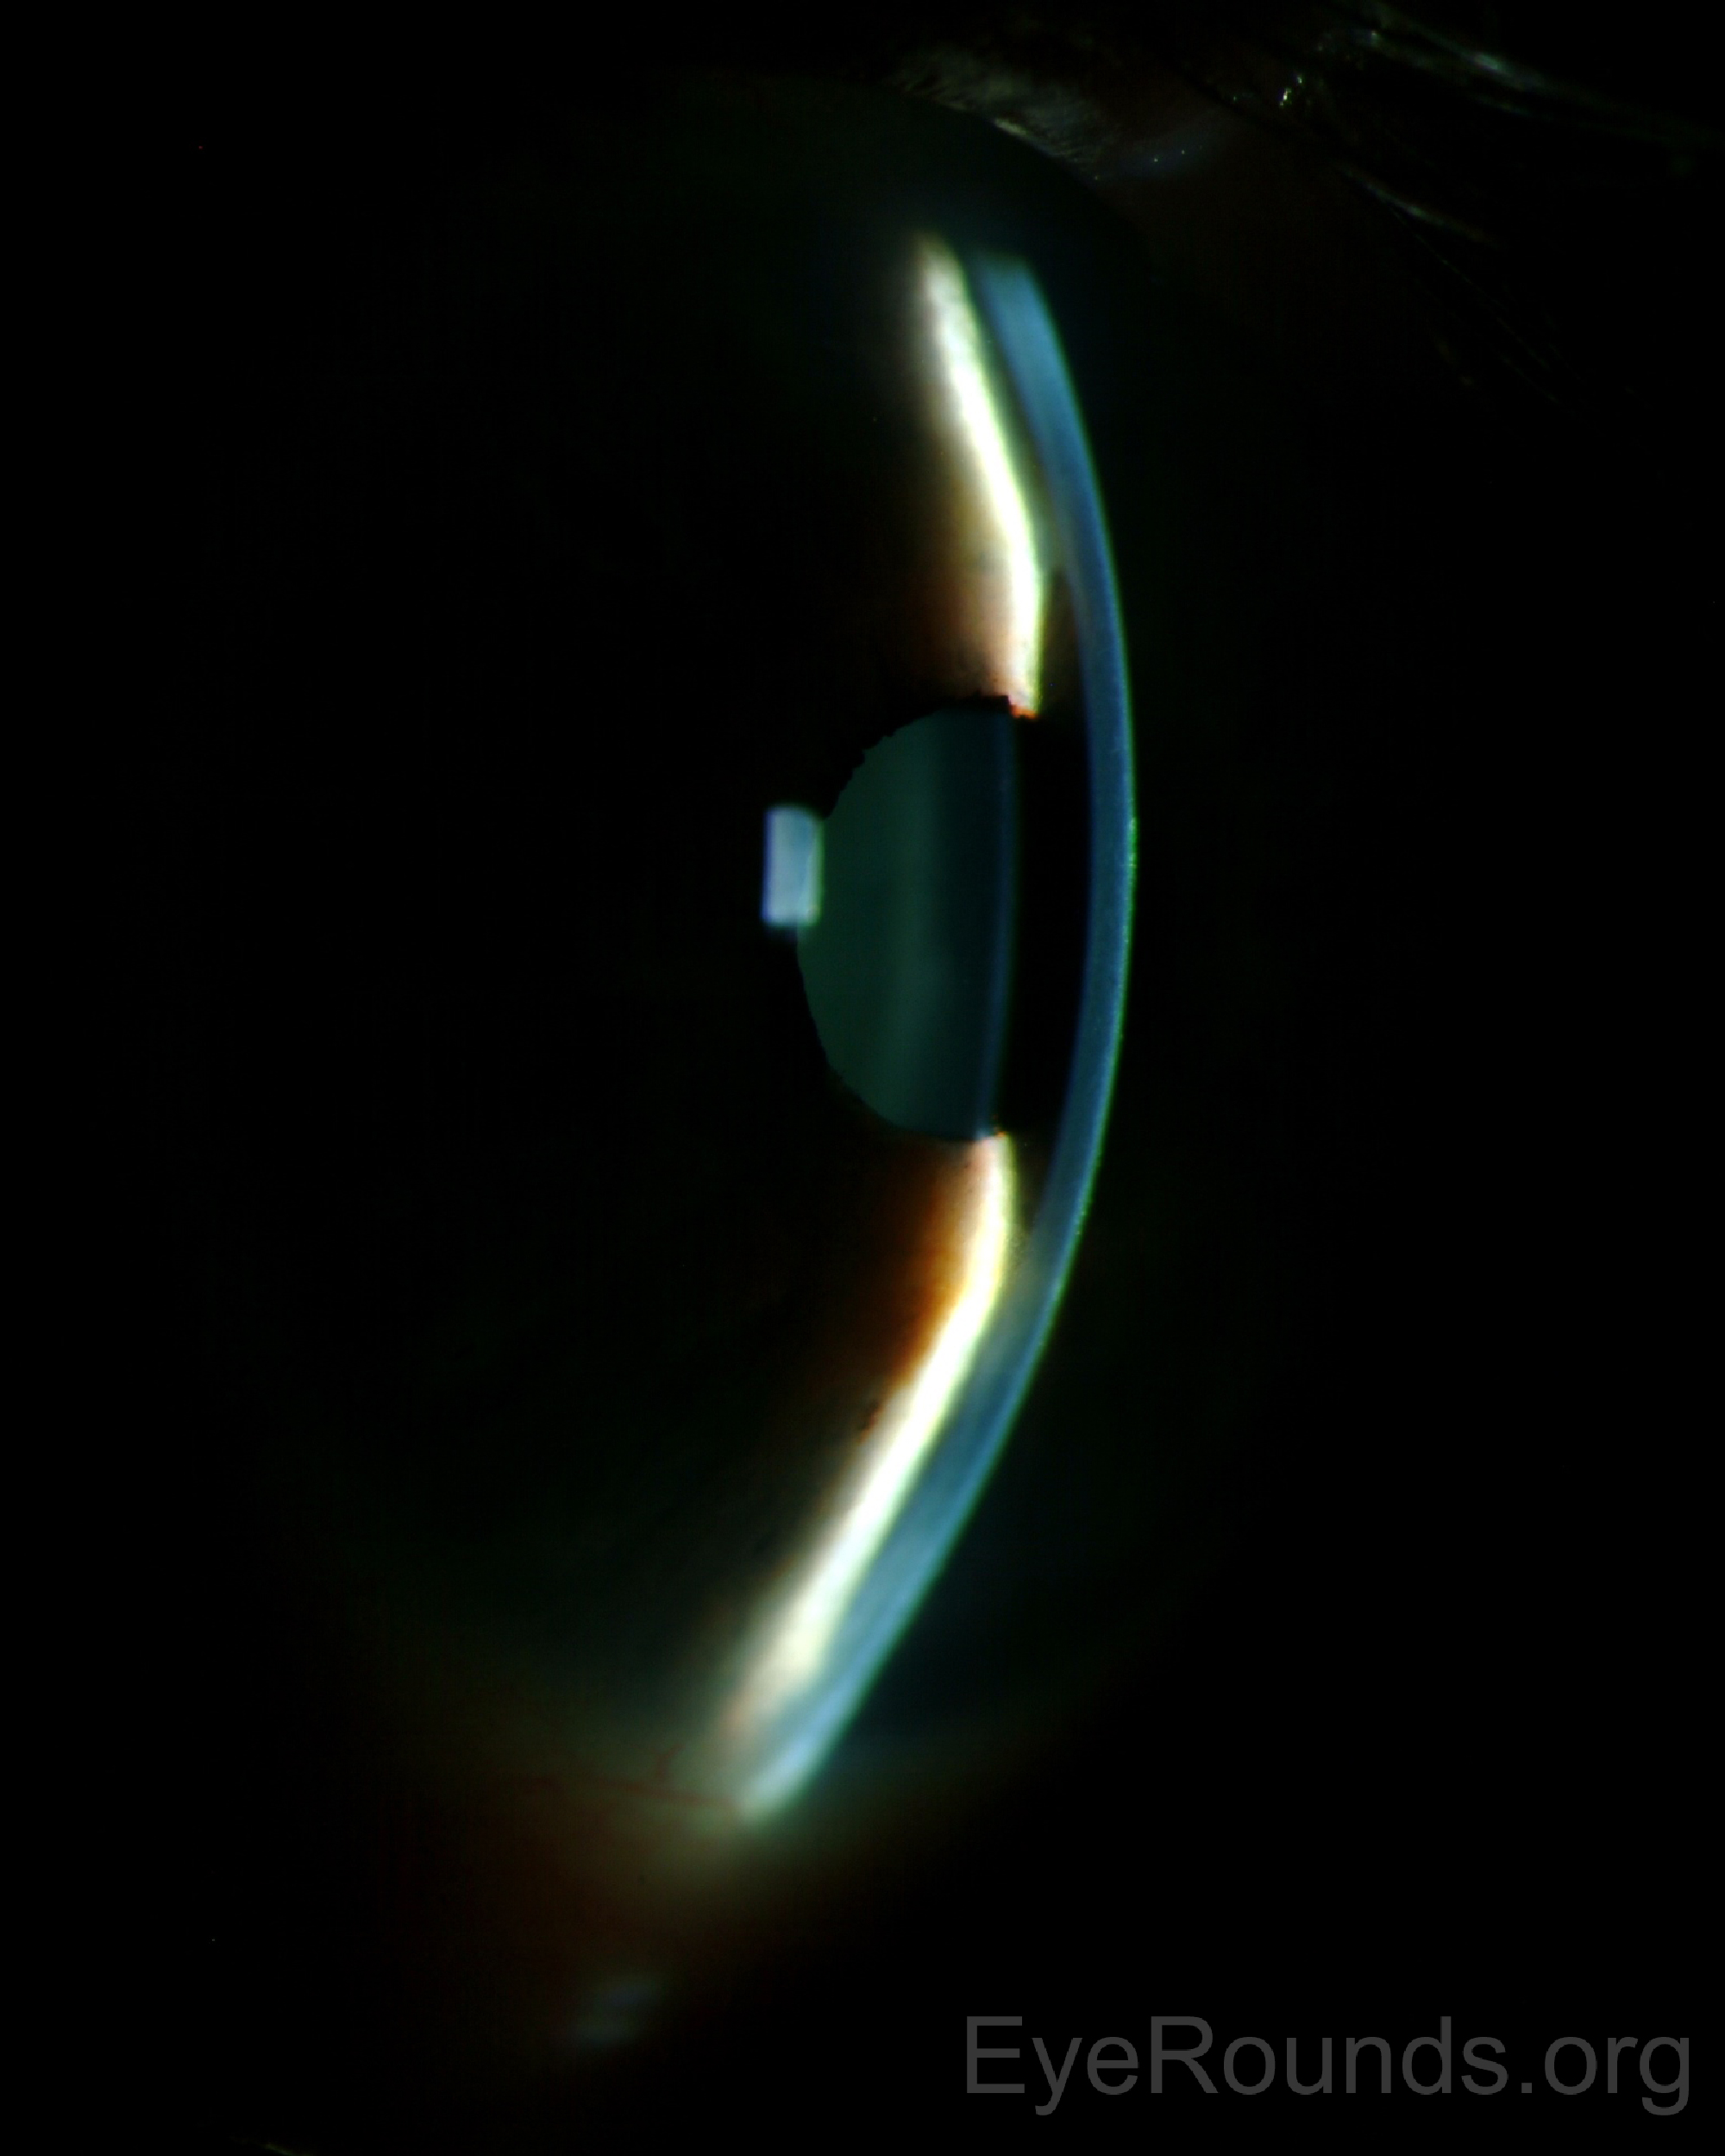

홍채-수정체 격막의 전방이동(lens-iris diaphragm anterior shift)이 발생하며,

전방이 소실되면서, 안압이 증가된 소견을 보입니다.

보통 2주 정도 기다려보면 고여있는 혈액이 응고되다가 다시 용해되게되는데,

이때 수술적 치료를 통해 공막절개를 하여, 고여있는 출혈을 제거할수 있습니다.